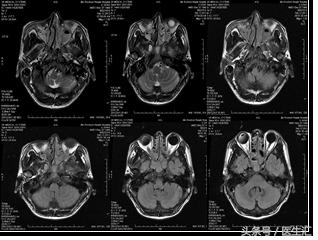

头部、腹部MRI 示双侧副鼻窦炎,肝硬化、脾大、门脉高压症(如下图)。